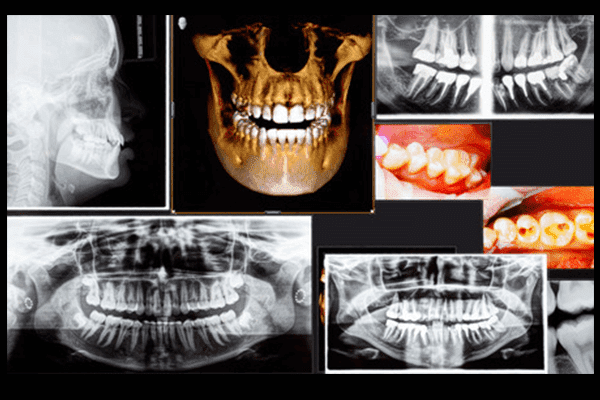

しかし、従来の2次元のレントゲンでは、平面のレントゲン画像で診断するため、難しい症例の診断が確実ではありませんでした。

当院では、最新のCTレントゲンを導入することにより、顎の状態を的確に把握し、抜くべきか抜かないべきか、安全な治療のためにはどのような処置をすべきかなどの診断をすることが可能になりました。

より安全で、確実な診断・治療を行うためにはCTはもはや欠かせない機器となりました。

CTレントゲン撮影による診断と、患者様からのヒアリングを丁寧に行うことで、その方へのベストな処置方法を選択します。

また、歯肉に埋まってしまっている親知らず(埋伏歯)の場合や、難症例の場合にはCTの撮影も行います。

顎の状態を確実に把握できるため、安全性の高い治療が可能です。